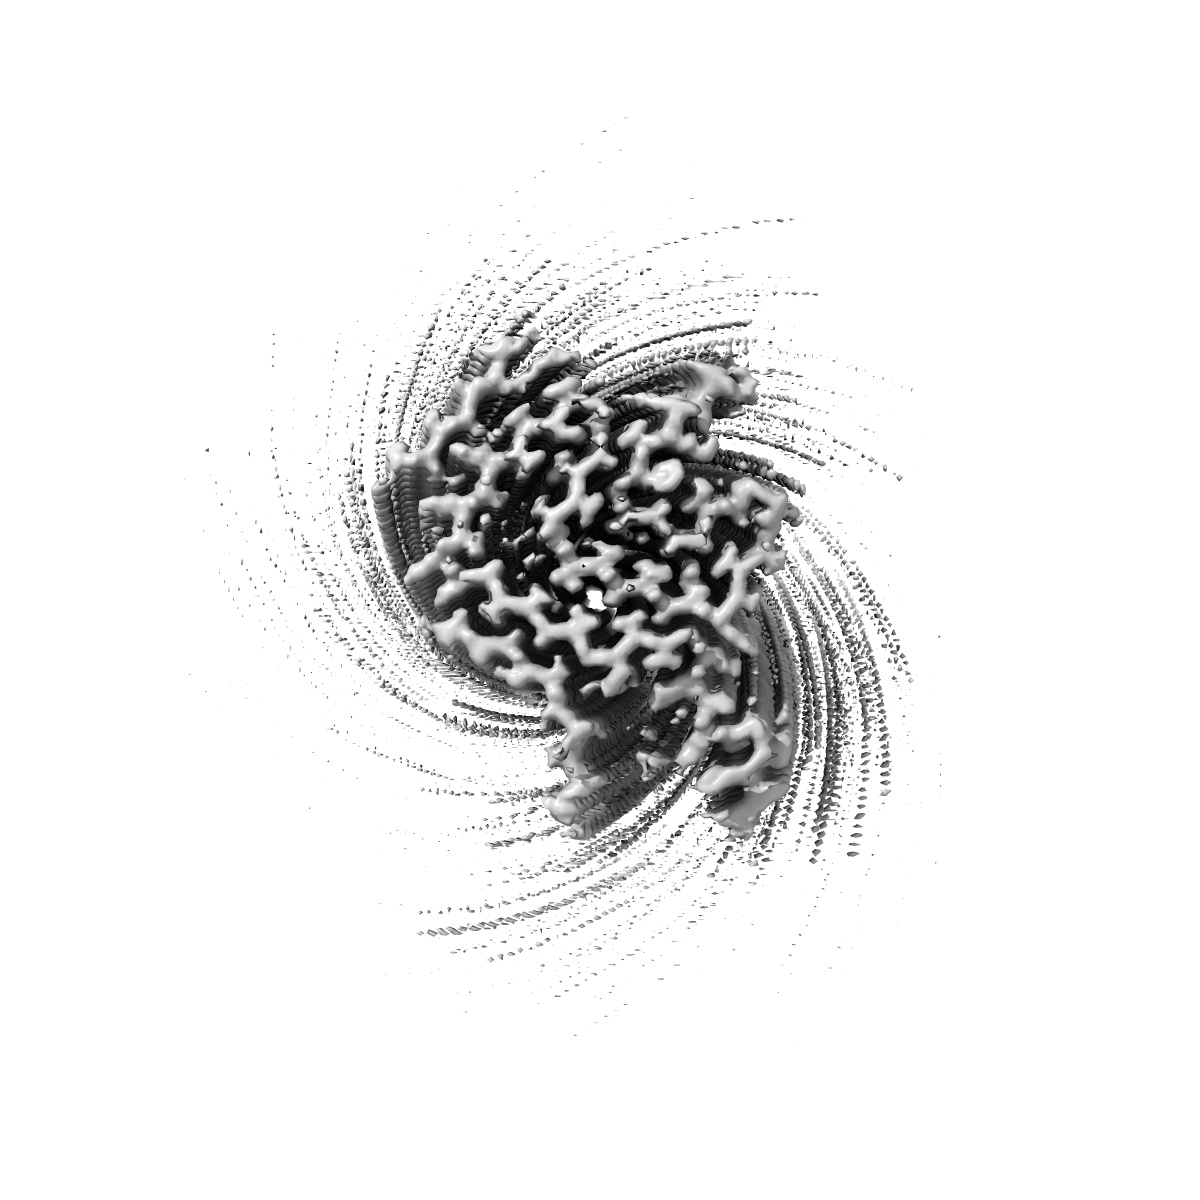

Cryo-EM structure of alpha-synuclein singlet filament from Juvenile-onset synucleinopathy

Helical reconstruction2.0 Å

Sample: Alpha-synuclein singlet filament extracted from the human brain with JOS